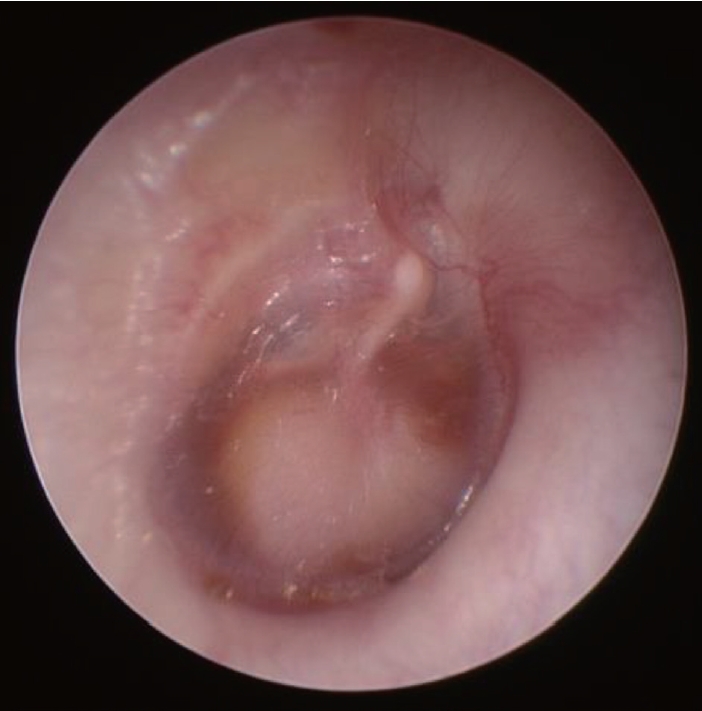

Fig. 1.

Otoscopic finding that shows a whitish mass medial to right tympanic membrane.

4세 10개월 나이의 여아가 우측 중이의 종물에 대한 진료를 위해 내원하였다. 아동은 1년 전부터 반복적으로 발생하는 우측 삼출성 중이염으로 거주지 인근 의원의 진료를 받던 중중이 종물이 의심되어 본원으로 전원되었다. 이내시경 검사에서 우측 고막의 중심부와 하방에 고막 전체 면적의 약 2/3를 차지하는 타원 형태의 백색 종물이 관찰되었다(Fig. 1). 순음청력검사에서 기도 청력(6분법 평균)은 우측 35 d B H L, 좌측 12 d B H L이었다. 환아가 차폐 검사를 수행하지 못해 골도청력검사는 시행하지 않았다. 이내시경 검사 소견에 근거하여 중이 진주종을 의심하고 측두골 전산화단층촬영을 시행하였다.